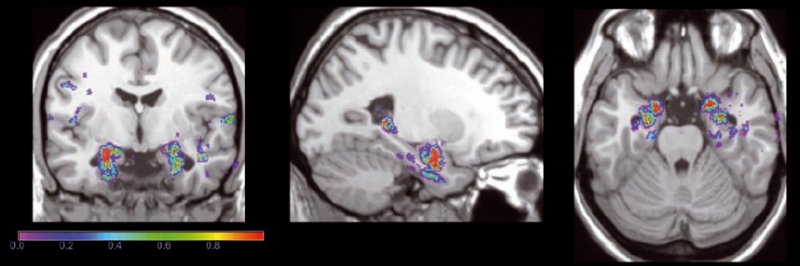

b.Sezione coronale (a sinistra), sagittale (al centro) e assiale (a destra) di una immagine di risonanza magnetica cerebrale. Le regioni in colore indicano le zone clinicamente rilevanti per la diagnosi precoce di soggetti affetti da malattia di Alzheimer.

Il progetto Mind, nato in collaborazione con alcuni ospedali di Genova, Trieste, Brescia e Perugia, vuole invece aprire nuove prospettive nell’ambito della diagnosi di malattie neurodegenerative cerebrali. Oltre all’Alzheimer, si parla anche della demenza fronto-temporale, del Parkinson e di altre ancora. L’estrazione di informazioni clinicamente rilevanti dalle immagini di Rmn e Pet, infatti, necessita di sofisticati strumenti di calcolo. Scopo di Mind è lo sviluppo di algoritmi di analisi di immagini cerebrali, per fornire al neurologo un ulteriore strumento di indagine, che potrebbe ridurre il rischio di errore diagnostico e rendere la diagnosi più precoce. Al momento, a questo scopo, i ricercatori stanno implementando un sistema compatibile con la Grid, ma più snello, già consolidato nel campo delle neuroscienze (il sistema Pipeline). Da febbraio 2013, grazie al servizio sviluppato dal consorzio europeo Decide, i neurologi potranno accedere a questa Grid, inserire le immagini Rmn e ricevere il risultato dell’analisi, che fornirà la probabilità che il paziente contragga la malattia di Alzheimer nei due anni successivi all’esame.